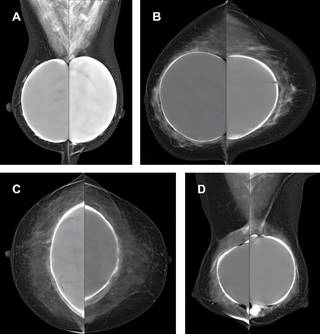

Con el paso del tiempo se forma una cápsula fibrosa delgada de tejido cicatricial alrededor de la prótesis como respuesta fisiológica, en algunos casos, se desarrolla proceso inflamatorio que causa que la cápsula pueda engrosarse o calcificarse.10 Algunos estudios han sugerido que la infección bacteriana de baja virulencia y subclínica podría ser un iniciador importante de proceso inflamatorio crónico que desarrolle la presencia de líquido y formación de seromas. Las cápsulas fibrosas en ecografía pueden verse como líneas hiperecoicas paralelas justo debajo de la interfaz del implante que corresponden a la envoltura formando el complejo cápsula-cubierta y el grosor normal de la cápsula suele estar entre 1 y 1.5 mm. En este estudio proponemos una clasificación mastográfica basada en grados para valoración de la cápsula fibrosa, determinando los cambios observados en nuestras pacientes, los cuales se describen en la Tabla 1 y Figura 2.

Figura 2: Grados de cápsula fibrosa de implantes mamarios valorados por mastografía. A) Mastografía digital bilateral medio oblicuo-lateral con presencia de implante de bordes regulares. Grado I . B) Mastografía digital bilateral cefalocaudal. Implante con engrosamiento capsular, mayor a 2 mm. Grado II. C) Mastografía digital bilateral en proyección cefalocaudal. Implante con bordes irregulares. Grado III. D) Mastografía digital bilateral medio oblicuo-lateral con calcificaciones gruesas periprotésicas y deformidad de la mama. Grado IV.

La contractura de la cápsula lleva a deformidad clínica de la mama con resultado cosmético adverso por retracción del tejido fibroso, esta es la complicación más frecuente, produce endurecimiento de la mama en grados variables y se ha relacionado estrechamente con el tipo de superficie del implante (lisa o texturizada), sugiriendo que la formación de una cápsula alrededor de las prótesis lisas promueve el desarrollo de dicha complicación. Con las prótesis texturizadas microporosas se ha demostrado una incidencia significativamente menor de contractura capsular y se suele observar entre 4-8 meses después de la cirugía, pero el riesgo se extiende con el tiempo. Hay hallazgos sugestivos de contractura capsular como cambio en la morfología del implante, engrosamiento de la cápsula, calcificaciones alrededor de la prótesis, superficie irregular y en casos avanzados franca asimetría en volumen. El diagnóstico suele ser clínico mediante la escala de Baker siendo el grado I una mama blanda de aspecto normal, grado II mama de consistencia firme, grado III mama firme con algún grado de distorsión visible, y grado IV mama sensible y dolorosa con franca distorsión. Aún no están documentados los hallazgos radiológicos específicos para valorar la cápsula fibrosa por imagen.11